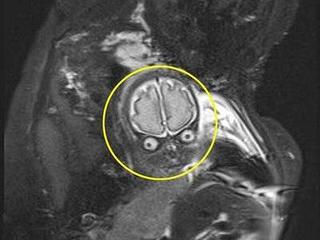

Hình ảnh em bé trong phim chụp cộng hưởng từ có sự giống nhau kì lạ với nhân vật trong bộ phim hoạt hình nổi tiếng: "Cuộc tấn công từ sao Hỏa".